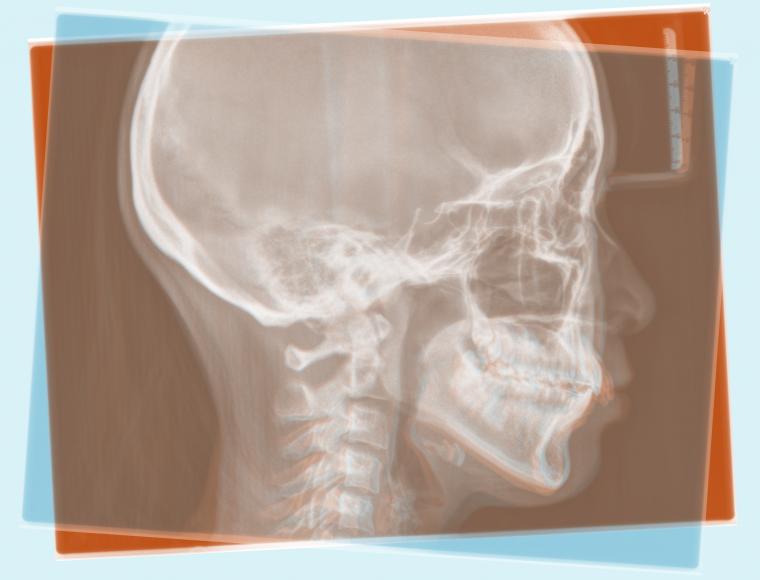

#51 矯正用インプラントアンカーを用いてオートローテーションを図った症例